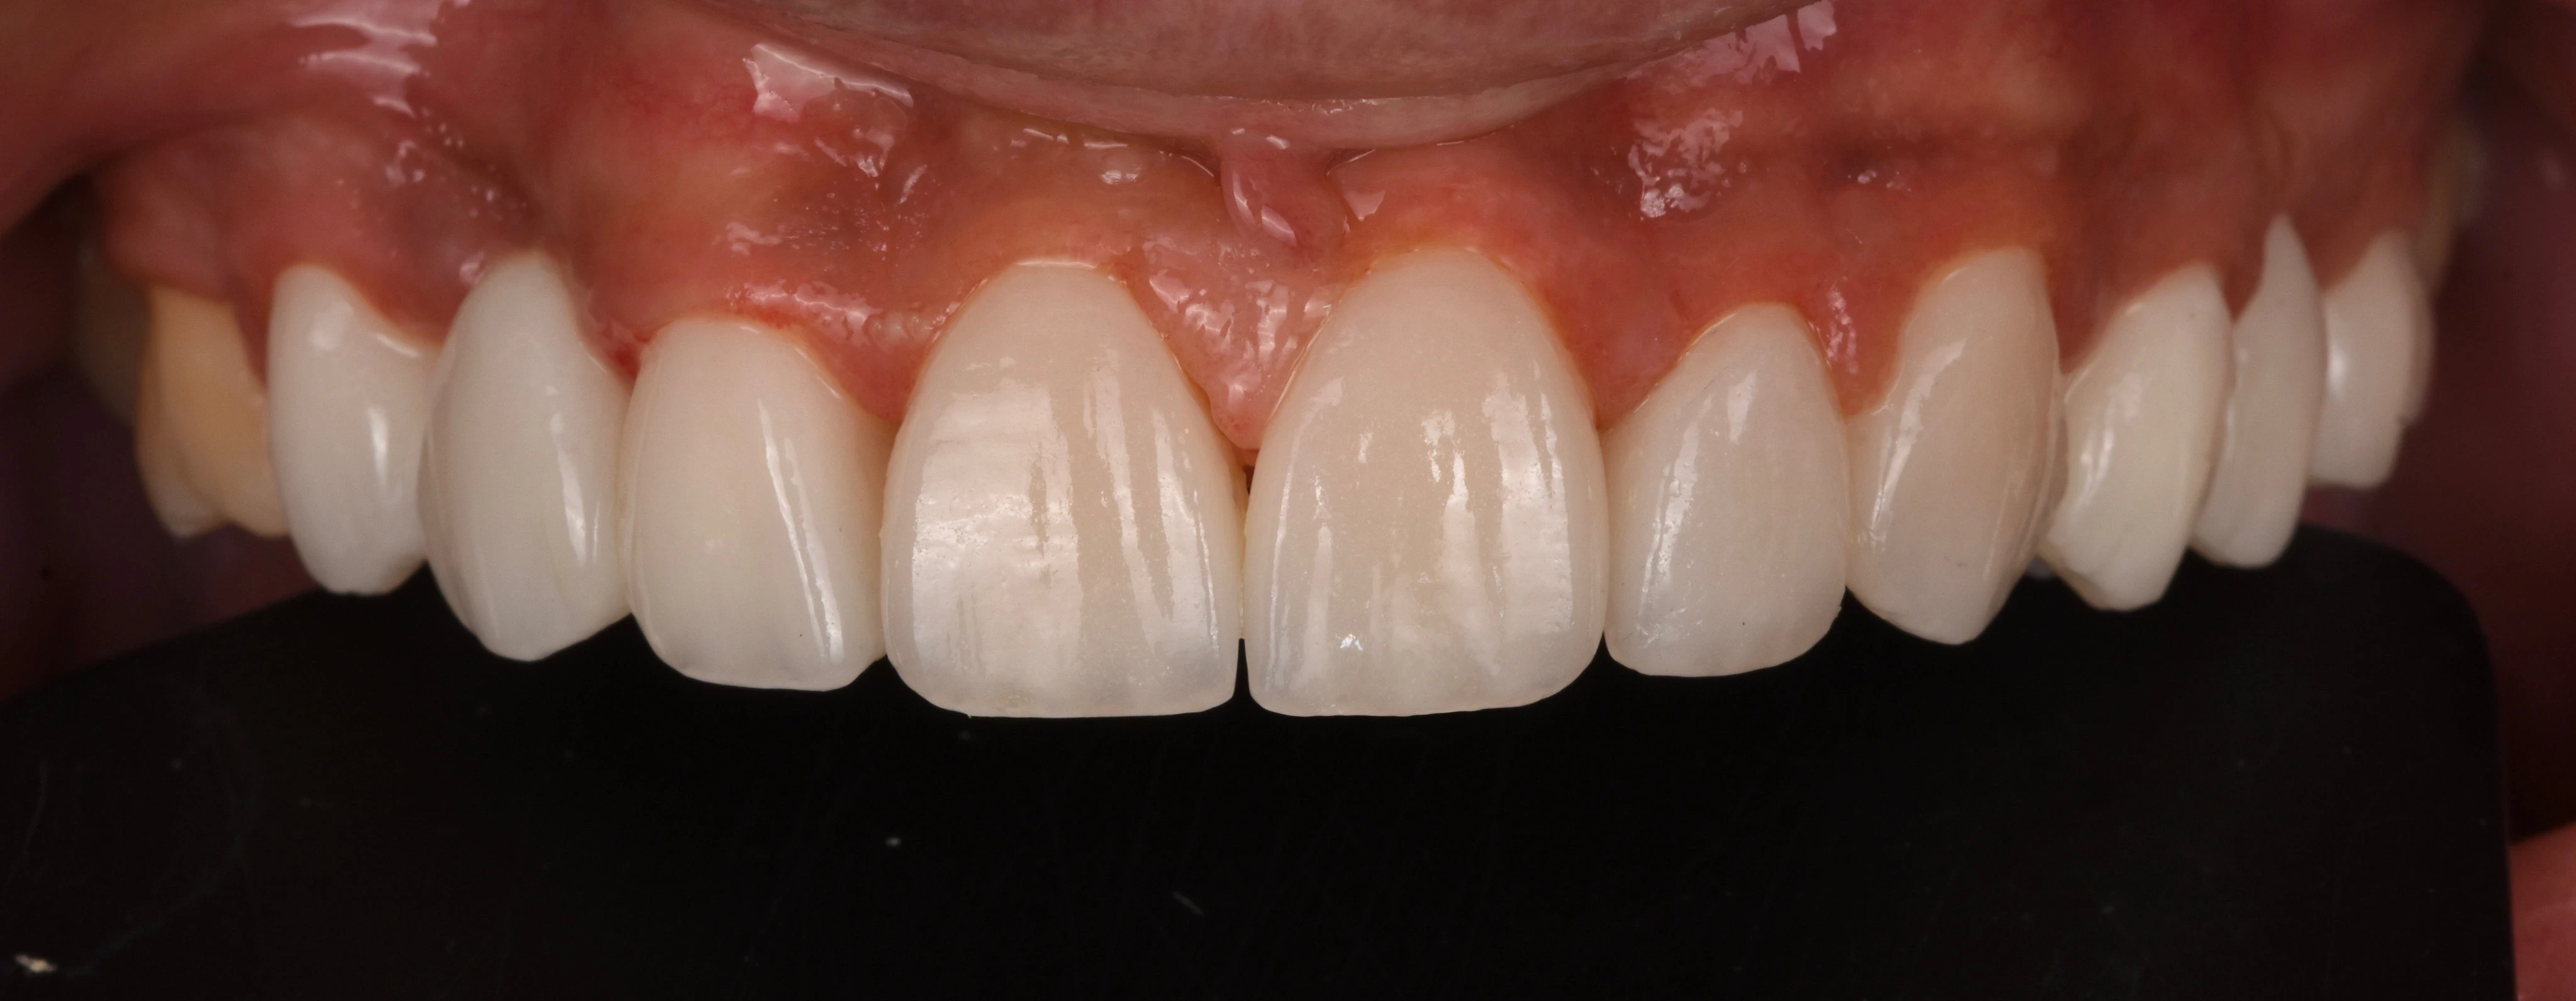

يلجأ الشخص إلى تحسين شكل أسنانه عن طريق فينير الأسنان أو ما يطلق عليه (عدسات الأسنان اللاصقة) وهي عبارة قشرة رقيقه يتم لصقها على السطح الخارجي للأسنان مصنوعة من مواد صلبة ذات معامل شفافيه مطابق للأسنان الطبيعيه   لعلاج مشكلة الاصفرار أو عدم التساوي والعديد من المشاكل الأخرى، حتى يحصل الشخص على ابتسامة رائعة تشبه ابتسامة نجوم هوليود.

• إظهار الأسنان بشكل أكثر جمالًا بعد تغطية كل عيوب الاسنان.

• المواد التي تصنع منها الفينير لا تسبب التهابات وتتقبلها اللثة.

• يحتفظ الفينيرز بلونه وخصائصه لأعوام عديده.